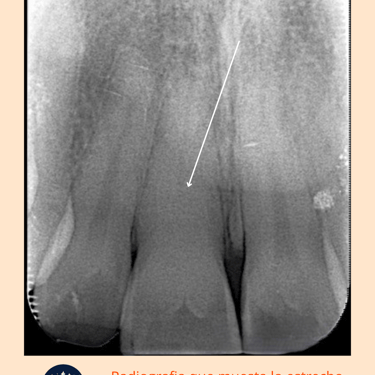

Las calcificaciones radiculares ocurren cuando se depositan minerales en los conductos radiculares, estrechándolos o bloqueándolos por completo. Este procedimiento es necesario para limpiar los conductos y realizar el tratamiento endodóntico.

Evaluación Inicial: Examen clínico y radiografías para identificar la presencia y extensión de las calcificaciones.